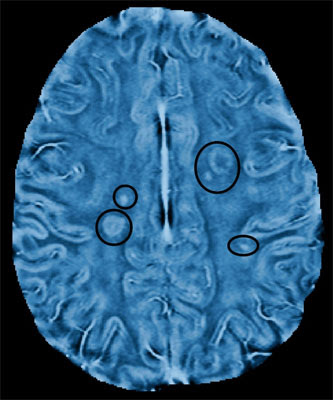

El sistema superpone y fusiona la información de imágenes de RM 3D con la capturada con ultrasonido. El tumor está contorneado dentro del software del sistema y luego es atacado con ultrasonido. La combinación del ultrasonido en vivo y de la resonancia magnética le permite guiar el haz de energía en tiempo real durante la terapia.